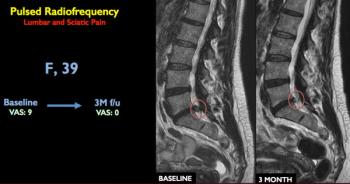

Patients can obtain relief from low back pain and sciatica with the use of image-guided pulsed radiofrequency treatments.